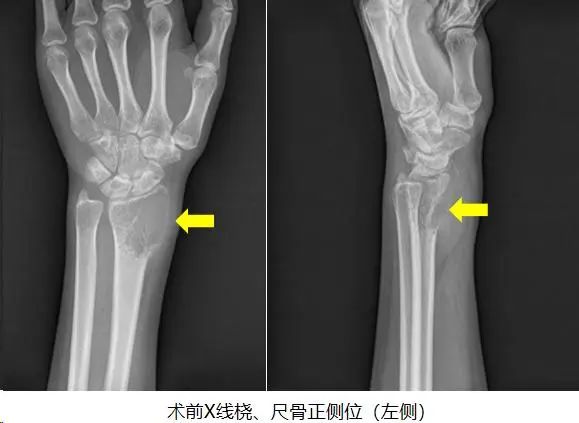

21岁的小英,一个多月前突然感觉自己左腕关节出现间断性疼痛,初期以为是运动时不小心扭伤,随着时间推移,她发现左手腕处居然长了一个质硬的包块,并到医院拍片后,发现左侧桡骨远端膨胀溶骨性破坏。随后曾到广州某三甲医院就诊,经过多番打听和比较后,选择来到我院骨质疏松与骨病骨肿瘤科外科门诊找到郑鸿主任就诊。

结合影像学检查结果以及病理穿刺结果,可以明确诊断为左侧桡骨骨巨细胞瘤 III级,首选手术切除病灶;且具有侵袭性的III级,则需要彻底完整切除肿瘤以及行桡骨重建手术。

经过精确测量发现,手术需要切除患者包括桡骨远端关节面在内的瘤段至少7cm,手术切除瘤体后桡骨局部缺损巨大,可以利用先进的3D打印技术,打印一个定制假体,匹配度高,手术时间较短且方便简单。